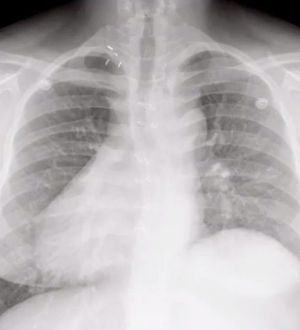

Dextrocardia

Does it also look enlarged, and the trachea deviated?

Agreed, It does look enlarged.